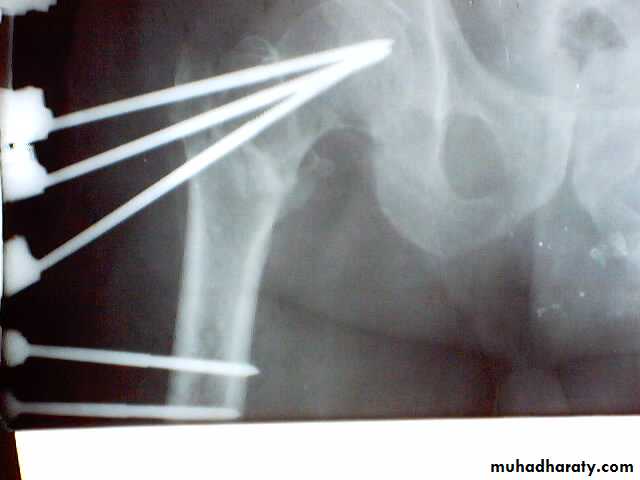

3.External fixation

Lower limbs